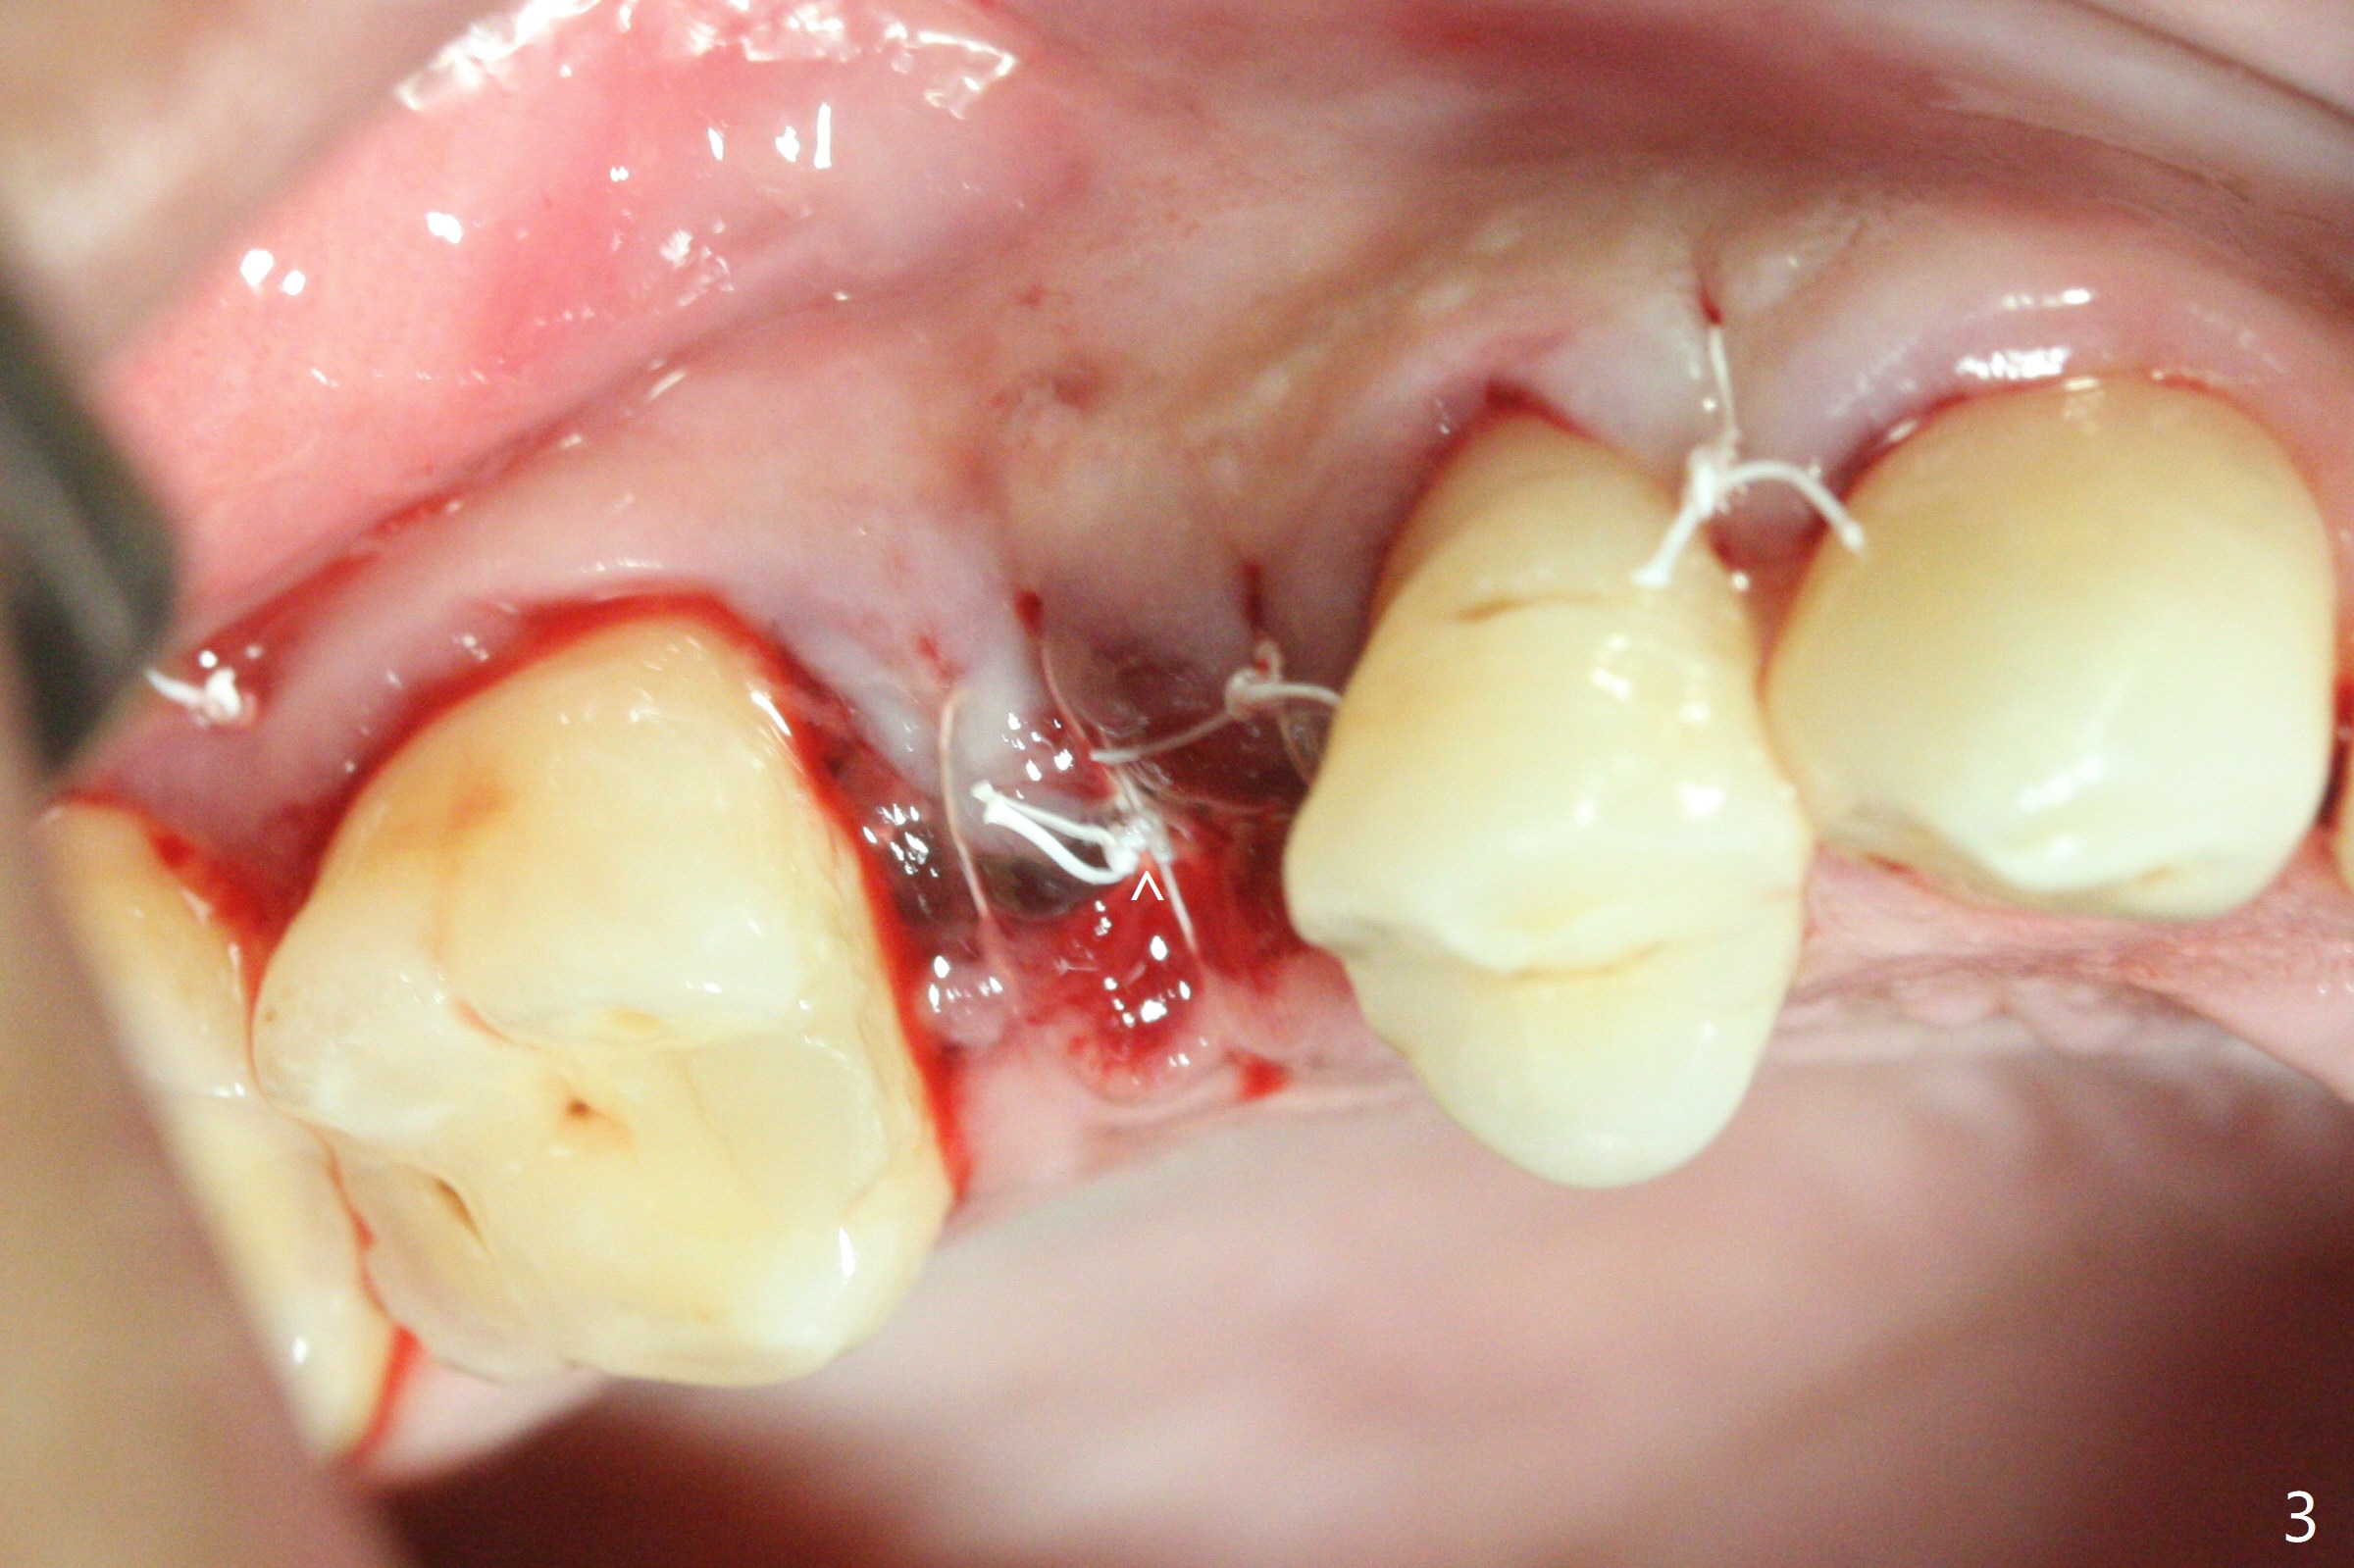

尽管没有任何症状,右上5牙冠粘固后2年5个月,牙冠与基台取出(没有使用扳手,说明基台未完全就位),切开,去除少量肉芽组织,仍然发现植体螺纹暴露(图一),使用一种叫I Brush 钛合金刷子清洁后,放置粘性骨块(图二: S),它坐在牙槽嵴上仿佛非常安稳,多么象马鞍(Saddle)。覆盖一张PRF膜和一小张Cytoplast(不可吸收膜,Osteogenics (company) 图三:箭头),使用PTFE缝线(与Cytoplast同样一种材料)缝合。术后即刻根尖片显示骨粉服服帖帖地坐落在植体和牙槽嵴上(图四:*)。最后覆盖牙周敷料。后者术后十天左右脱落,伤口愈合正常,颊侧瘘道仿佛消失,颊侧骨壁好像不再凹陷了(图五,六)。术后5周,膜已经脱落,缝线撤除后,伤口好像二期愈合,但愿肉芽组织下面骨粉尚未损失太多。术后三个月根尖片显示骨粉减少(图八)。不可吸收膜脱落可能造成骨粉流失。应该做减张缝合。术后4.5个月颊侧骨壁又凹陷(图九:箭头,需要decortication),但是uncover时植体周围都有骨质包绕,术后咬翼片也证明近中,远中骨质接触植体(图十:由于找不到合适愈合基台,直接放置基台和牙冠)。粘固后2.5个月虽然颊侧骨板凹陷,但是没有植体周围炎迹象(图十一)。